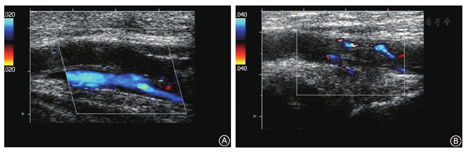

术后第8天晚,患者突发双侧腹股沟区、腘窝至小腿后内侧放射性绞痛,予以杜冷丁肌内注射后缓解。次日膝关节周围轻度胀痛,双下肢无淤血及肿胀,肢端血运良好,考虑功能锻炼引起,继续予以镇痛处理。第11天,血小板计数34.4×109/L。术后第13天,双侧腘窝及小腿胀痛加剧,双下肢皮温稍低,足背动脉搏动减弱。急查双下肢血管彩色超声检查显示双侧腘动脉不全栓塞(图1)。请血管外科会诊,继续低分子肝素治疗,加用盐酸沙格雷酯片(100 mg,3次/d)抗血栓、红外线照射(2次/d)。第14天,患者出现轻微头痛,无恶心、呕吐,未予特殊处理。第16天血小板计数57.4×109/L,继续低分子肝素治疗。当晚患者头痛加剧,伴恶心及喷射状呕吐,颅脑MRI示脑静脉窦栓塞(图2),血压190/100 mmHg,随后出现休克、神志不清、深度昏迷,经抢救无效死亡。

本例应用低分子肝素抗凝至术后第11天时血小板计数减少至34.4×109/L,术后第14天双下肢动静脉彩超检查发现双下肢腘动脉不全栓塞及术后第16天颅脑MR静脉血管检查发现脑静脉窦血栓,能除外其他原因引起的血小板减少,4Ts评分为8分,基本可确诊为HITT。治疗期间血小板计数明显下降,且先后出现双下肢疼痛及头痛,但未能尽早行下肢血管超声及颅脑血管造影检查,没有及时诊断HITT及停用低分子肝素,导致范围较大的血栓形成。HITT的预后与诊断的时间有关,越早发现和治疗,预后越好。临床医生应加强对关节置换术后应用低分子肝素抗凝导致血小板减少症的认识,严密监测血小板计数,做到早期诊断和及时治疗。